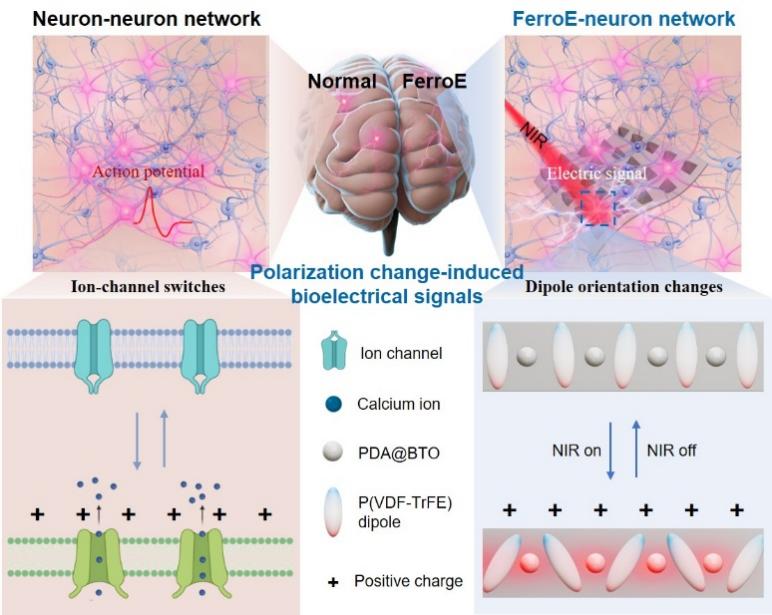

Jun 10, 2025Novel Neuron-like Ferroelectric Bioelectronics Enable Seamless Integration and Adaptive Communication with Neuronal NetworksThe study introduces a novel neuron-like interface materials and bioelectronics, ferroelectric bioelectronics (FerroE), which combine neuron-like flexibility, surface topography, and functional beh... Implantable bioelectronics are vital to neuroscience, neurological therapies, and brain-machine interfaces, serving as indispensable interfaces that enable communication between biological systems ...